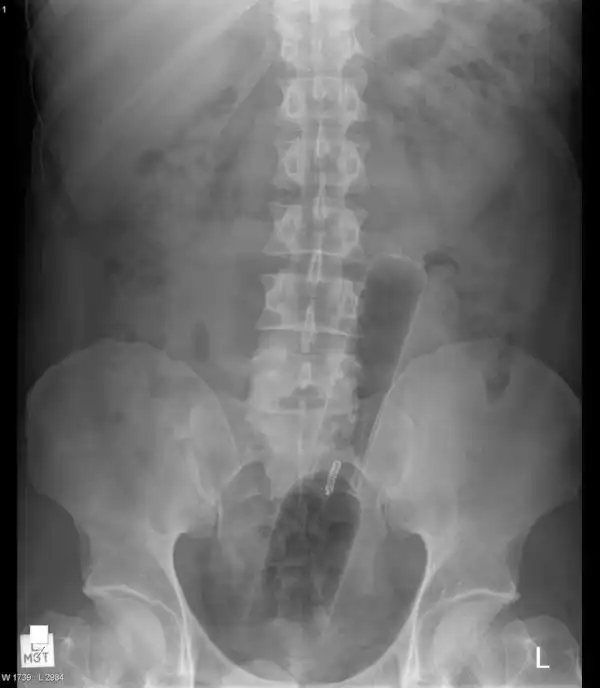

Врачебные находки в интимных местах

Или как впихнуть невпихуемое :lol: